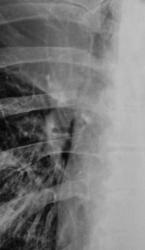

На иллюстрациях 1, 2. Представлены флюорограммы, произведенные в «настоящее время». На флюорограмме, произведенной в прямой стандартной проекции, визуализируется снижение прозрачности легочной ткани верхней доли правого лёгкого однородной структуры, без четких контуров. Правый корень несколько подтянут кверху, что навело на мысль об ателектазе. На боковой флюорограмме дифференцируется снижение прозрачности верхней доли средней интенсивности, однородной структуры с четкими «вогнутыми контурами», имеет место уплотнение структур корня с «кажущейся тяжистостью» кпереди, в средней доле. В грудном отделе позвоночника явления межпозвонкового остеохондроза.